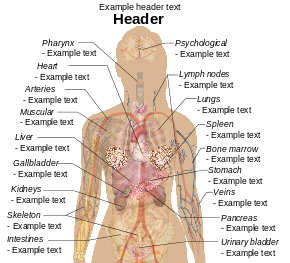

English: Main symptoms of different variants and stages of tuberculosis (See Wikipedia:Tuberculosis), with many symptoms overlapping with other variants, while others are more (but not entirely) specific for certain variants. Multiple variants may be present simultaneously.

Pulmonary tuberculosis symptoms

Extrapulmonary tuberculosis symptoms